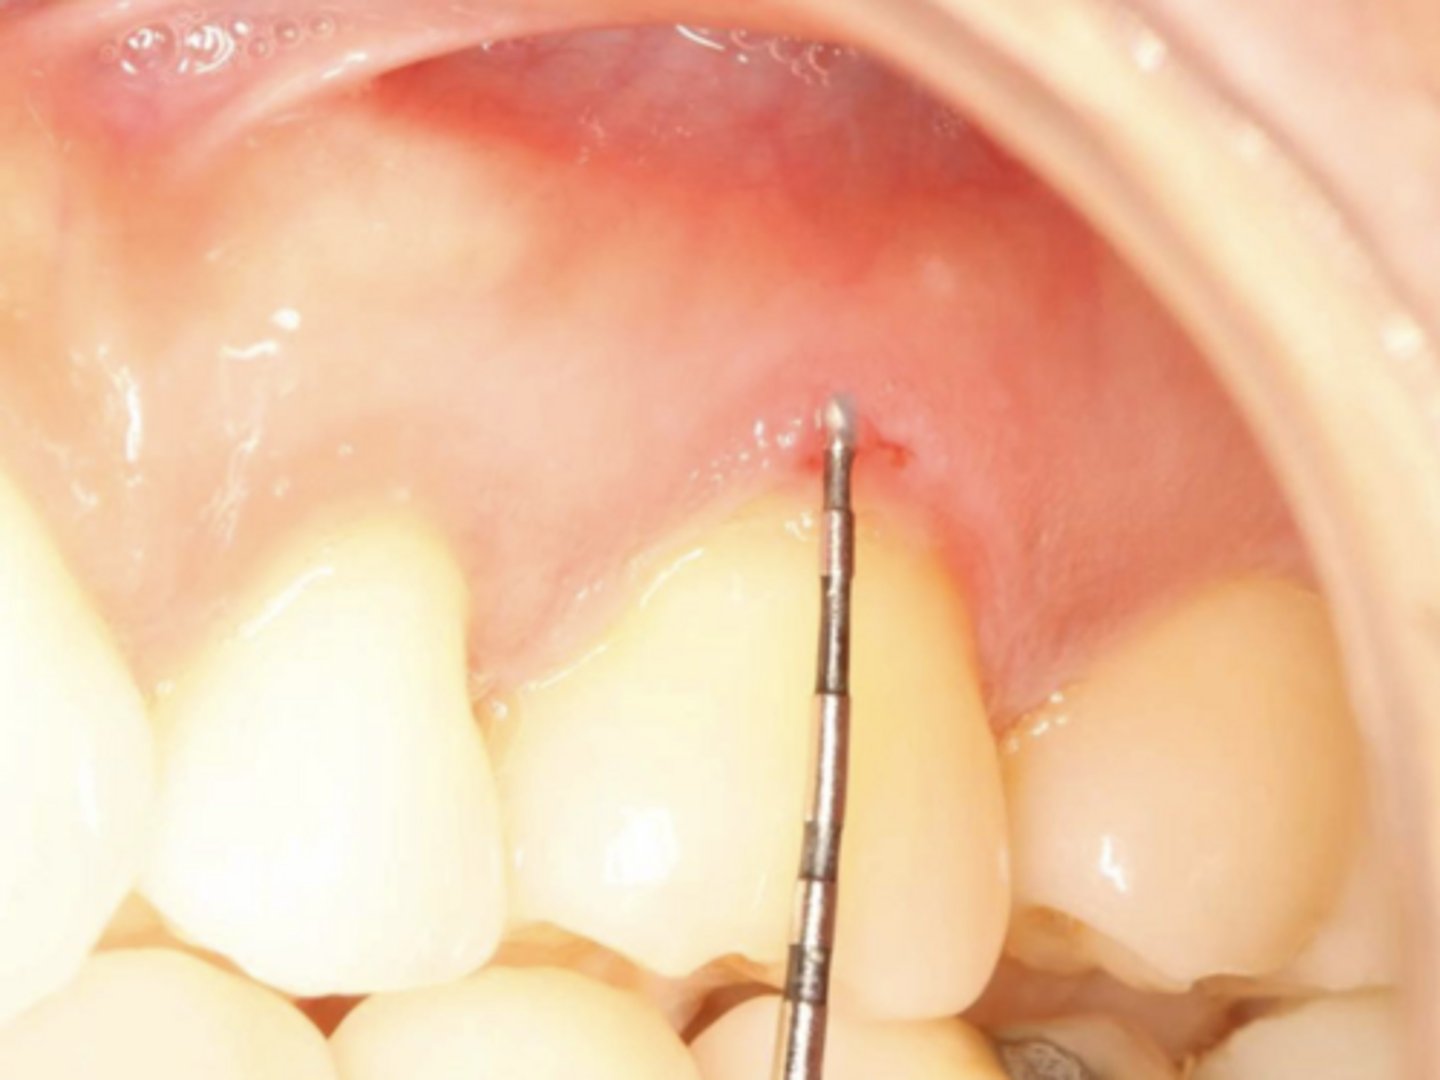

Mucous Membrane Pemphigoid

These are clinical features of what condition?

- Often restricted to gingiva

- 25% with oral lesions develop eye lesions

- Positive Nikolsky sign

Patient presents with these lesions along with ocular lesions including symblepherons, entropions, trichiasis. What is the most likley differential?

Patient presents with an autoimmune disorder with autoantibodies to hemidesmosomes. What condition do you suspect?

Patient presents with these lesions along with ocular lesions and an autoimmune disorder with autoantibodies to hemidesmosomes. What condition do you suspect?